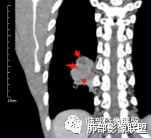

一般来讲,鳞癌收缩力弱,胸膜凹陷及牵拉少见,空洞坏死多见,而此例出现了“胸膜凹陷”,如下图:

这种特点在鳞癌比较多见  周围型鳞癌经常这个形态,外周有类似喇叭样收缩形态,考虑周围型鳞癌引起局部肺不张,所以有远侧内收而缺乏侧面收缩力。

回头看发现肿块近肺门侧边缘清楚,而远肺门侧边缘模糊,多考虑肿块阻塞支气管引起的阻塞性炎症,支持周围性鳞癌引起局部肺不张观点,两者形态相似,易与胸膜凹陷征混淆,小编认为,因肺不张为实变的肺组织,而胸膜凹陷为脏层胸膜受肿块牵拉凹陷形成的含液腔隙,故鳞癌形成的“胸膜凹陷”其密度较高,多为实性密度,而真正的胸膜凹陷征其内部密度较低,多为液体密度。